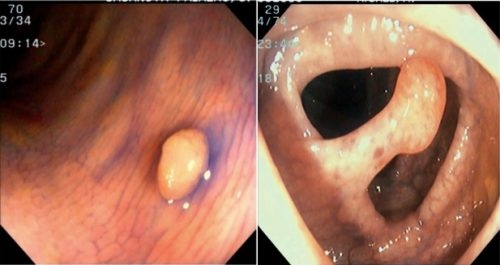

Polyp trực tràng có 2 dạng: Polyp có cuống và không có cuống

Những loại polyp không có cuống thường có chân rộng và không có sự xuất hiện của cuống, còn đối với dạng polyp có cuống thì có chân nhỏ và cuống dài.

Để biết được hình dạng và kích thước hiện nay các bác sĩ thường áp dụng phương pháp nội soi đại trực tràng. Tuy nhiên số lượng và kích thước của polyp đại tràng ở mỗi người là khác nhau, có người có thể có một hay nhiều polyp, cũng có người có polyp nhỏ nhưng ở người khác thì polyp đã phát triển ra to và mang khối lượng lớn hơn.